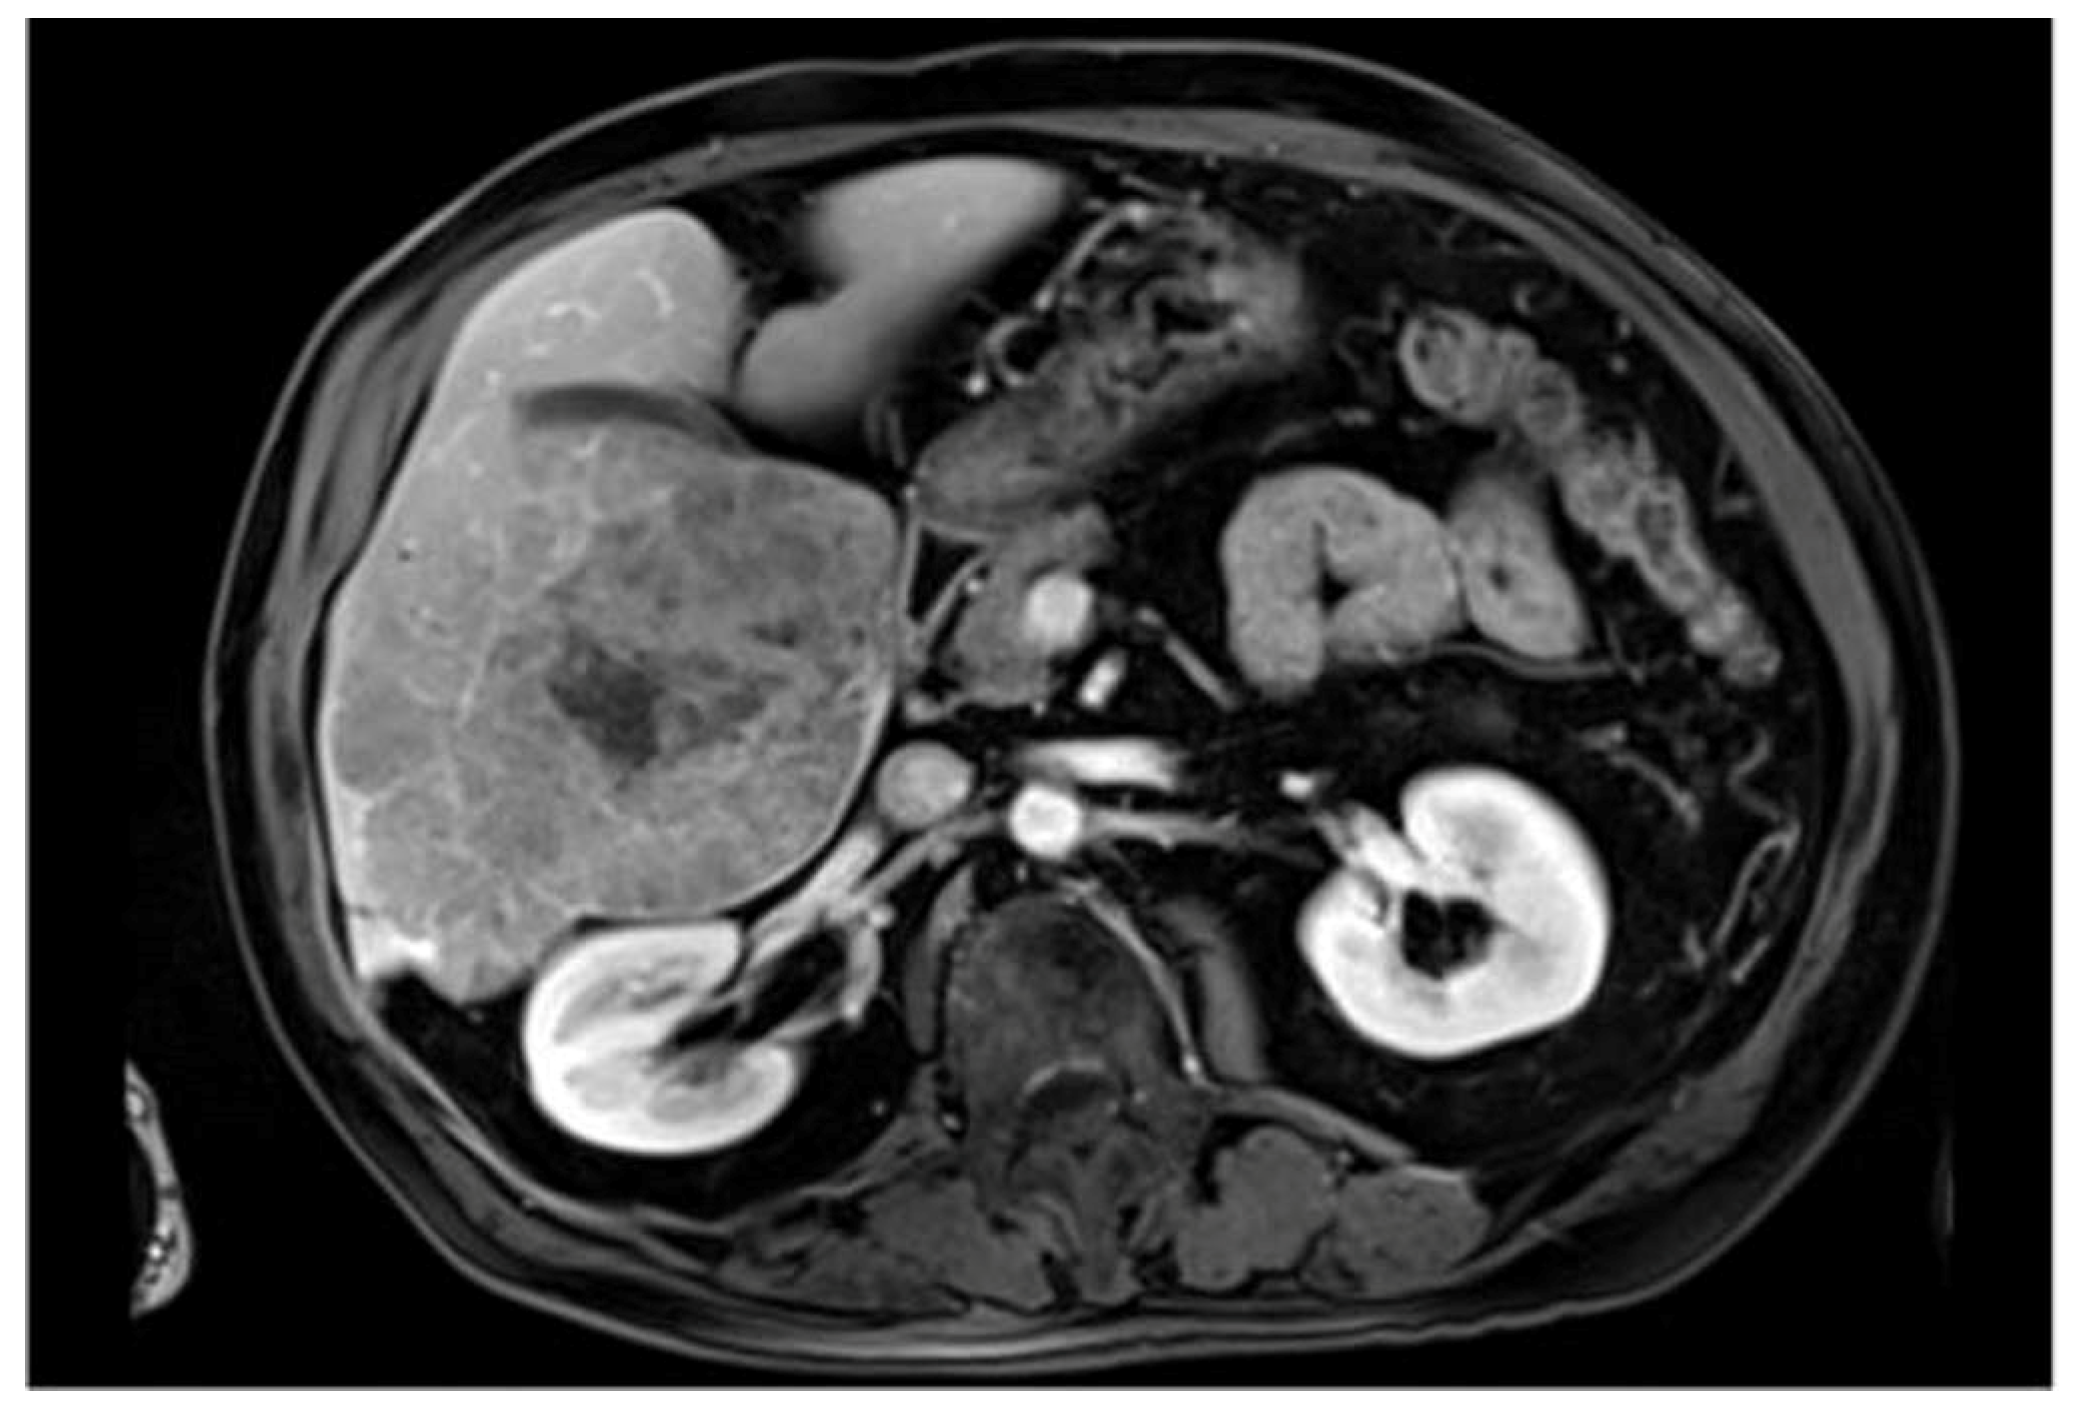

:1. Introduction

4. Development and Evolution of Liver Segmentation Technology

Early Methods

5. Threshold and Region-Growing Methods

6. Edge- and Shape-Based Methods

7. Deep Learning and Fully Convolutional Networks

8. Advances with U-Net and Variants

9. Integration of Emerging Technologies